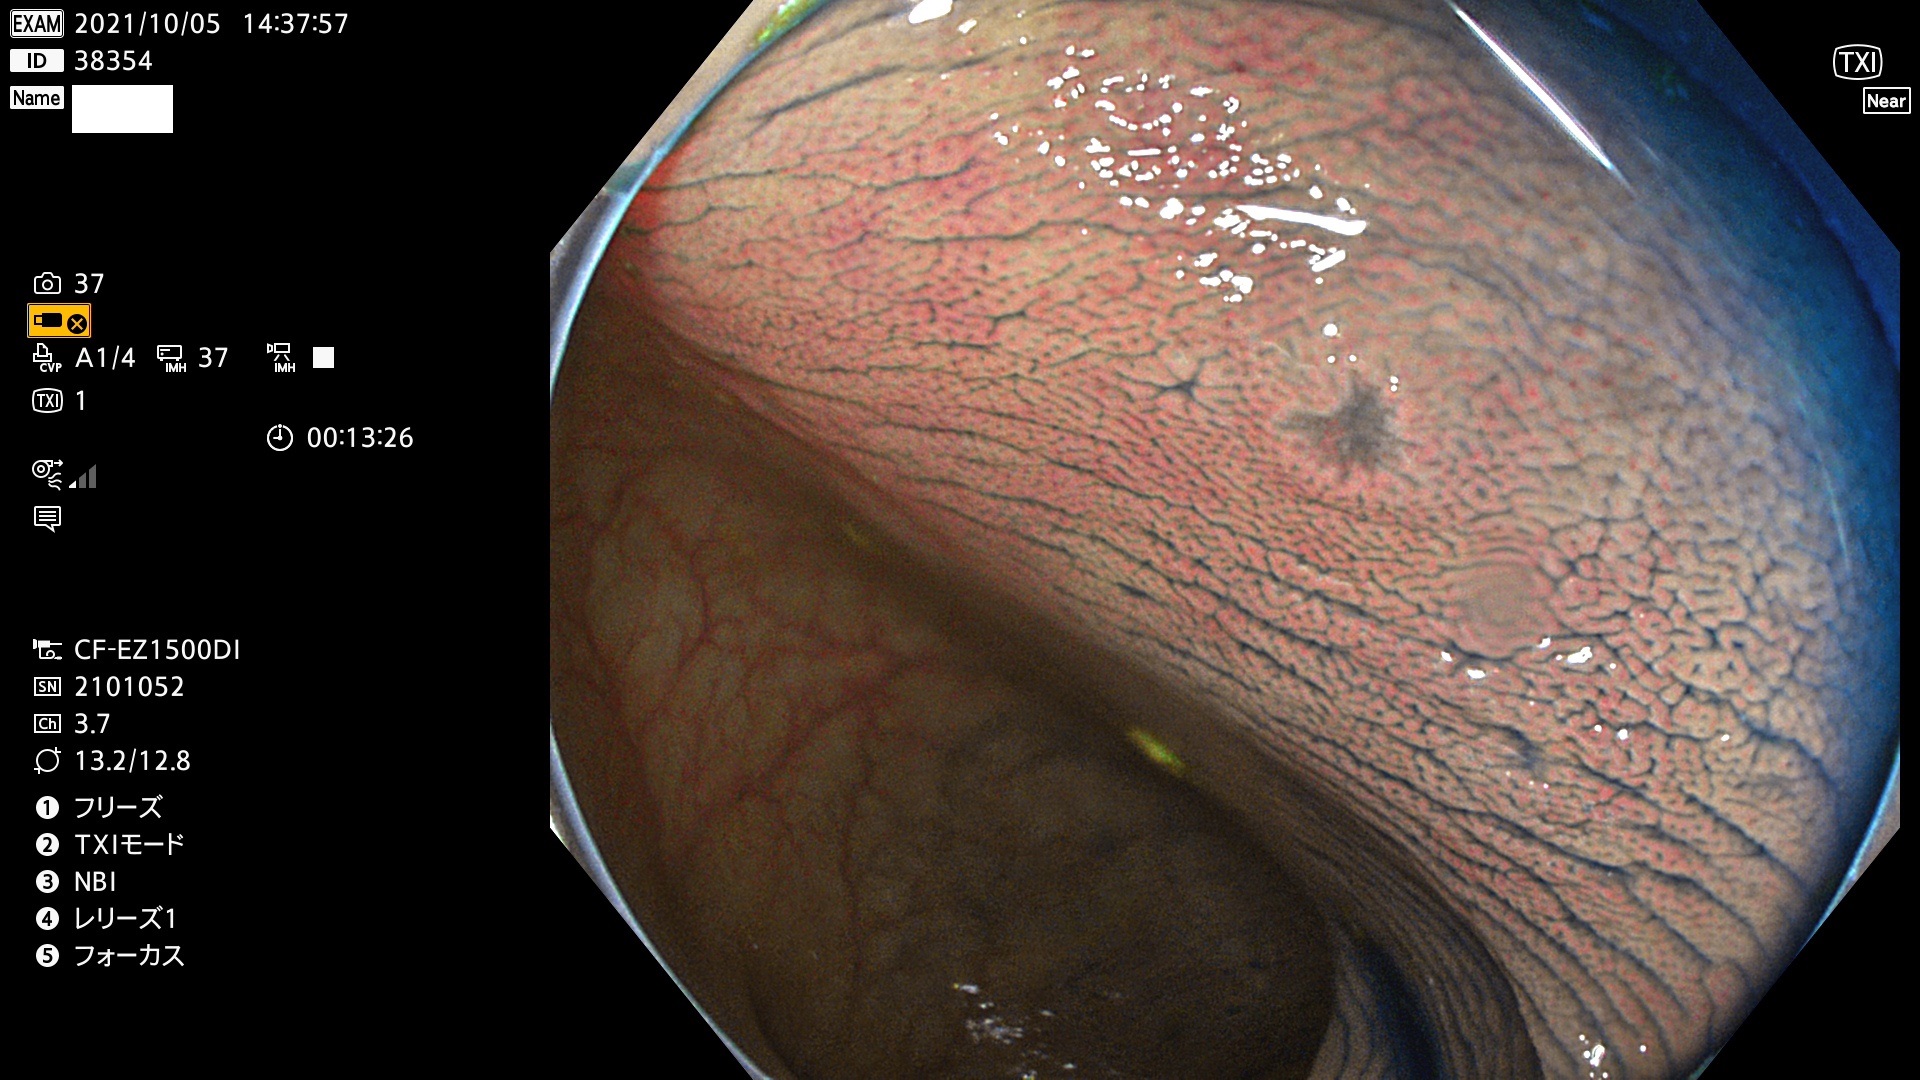

38300 38301 38302 38303 38304 38306 38307 38308 38309 38310 38311 38312 38313 38314 38315 38316 38317 38319 38321 38322 38323 38324 38325 38327 38331 38332 38333 38334 38337 38338 38339 38340 38341 38343 38346 38348 38349 38350 38351 38352 38353 38354 38355 38358 38359 38360 38361 38362 38363 38365 38366(SSAP) 38368 38369 38370 38371(SSAP) 38372 38374 38375 38376 38377 38378 38380 38381 38382 38383 38384 38385 38386 38388 38389 38391(SSAP) 38395 38397 38399

発見困難で危険性の高い平坦型病変(上記100名より抽出)